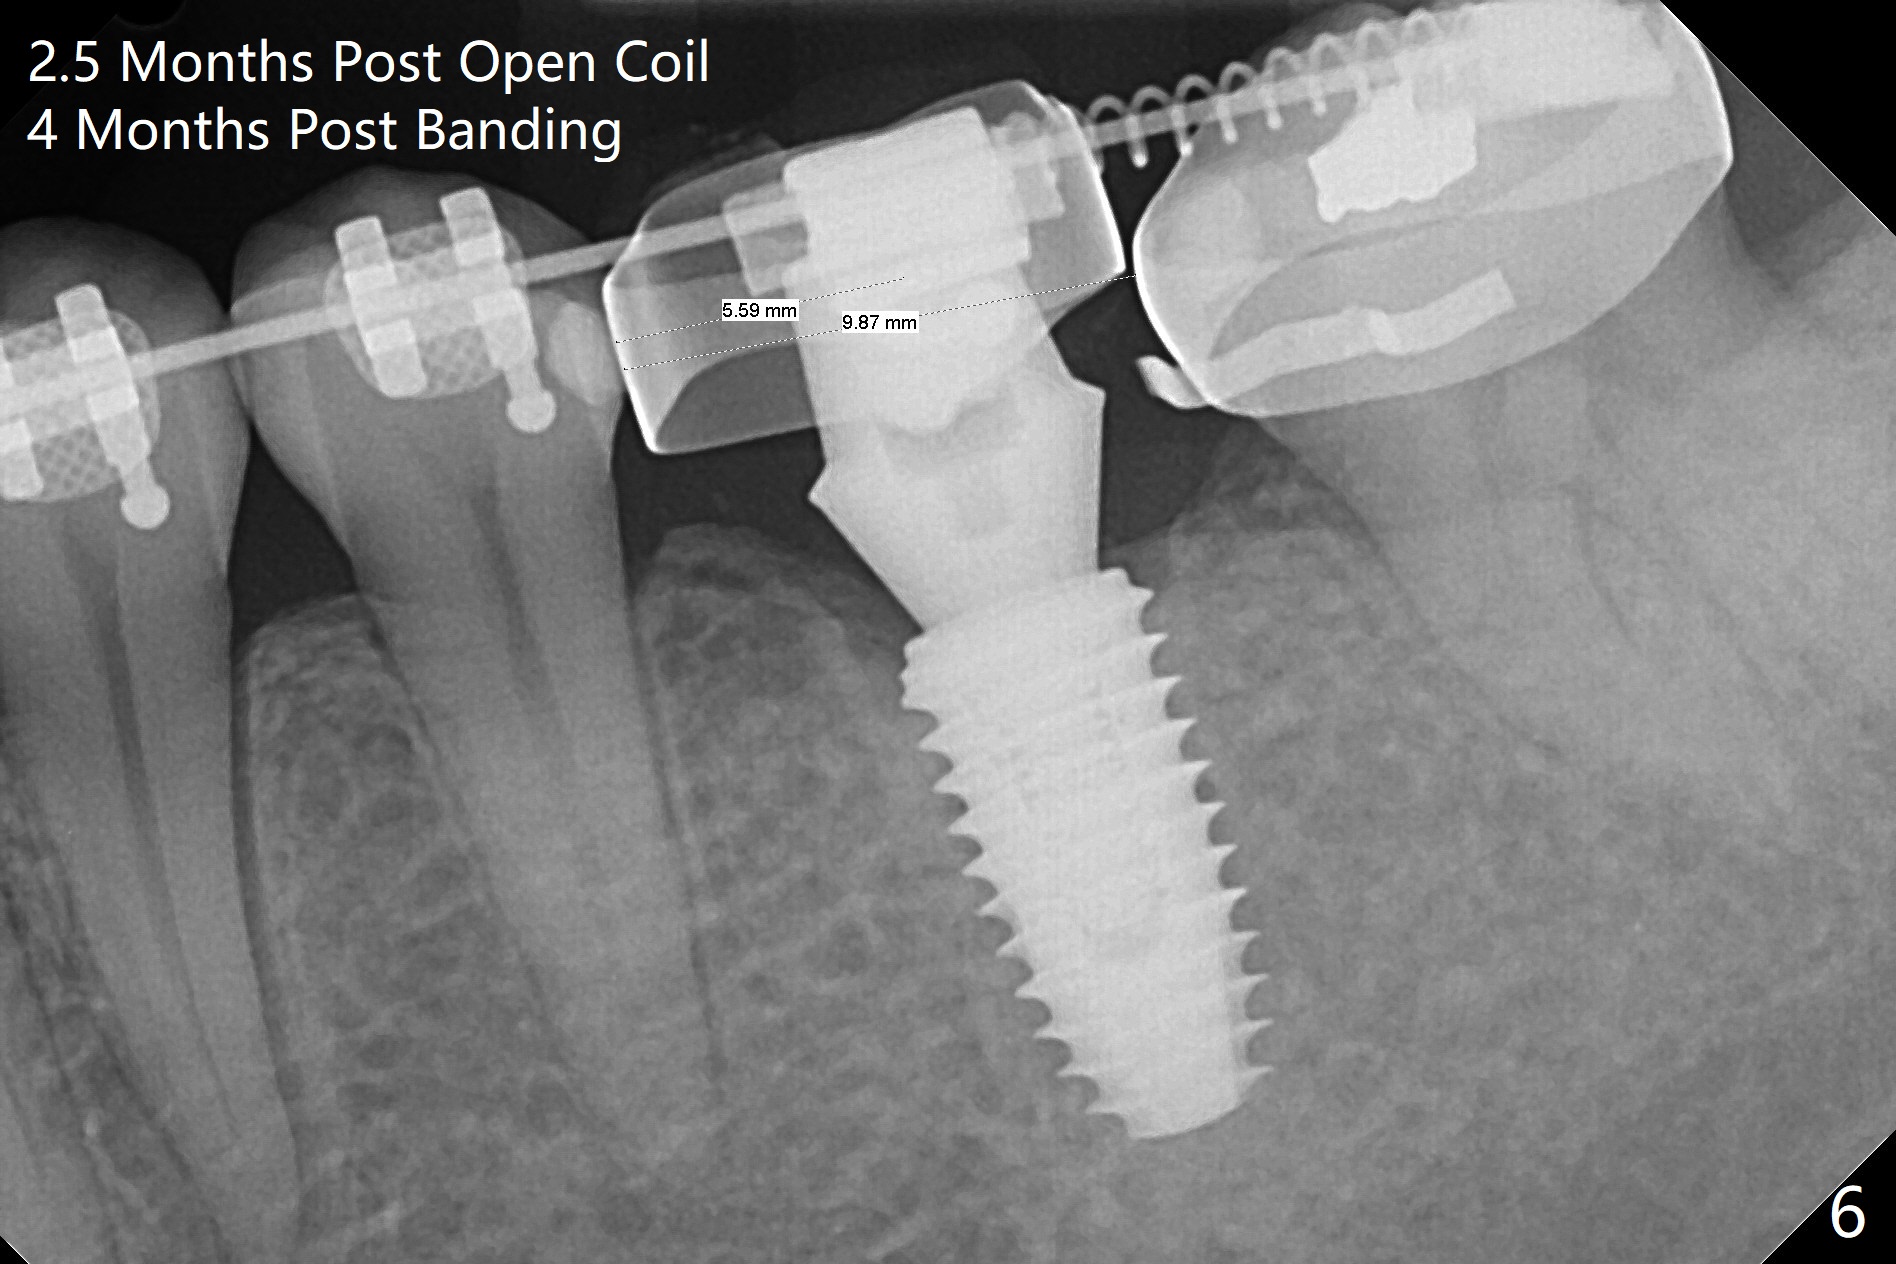

A 5x10 mm implant is intentionally placed distal at #19 using guided surgery (Fig.1). When it is osteointegrated, it will be used as an anchorage to upright the tooth #18 orthodontically. In fact the implant is mistakenly placed 1.5 mm deeper than planned without significant side effect (red dashed line: the superior border of the Inferior Alveolar Canal). The tooth #17 will be extracted before banding. The healing abutment dislodges (probably as related to deep placement of the implant) 20 days postop and is retightened. There is mild crestal bone loss 4 months postop (Fig.2). The tooth #17 is extracted with insertion of Osteogen Plug to prevent dry socket. A 5x4(2) mm cementation abutment will be placed with fabrication of a provisional with equi- or slightly subocclusal. Bands and brackets will be placed at #18-22. When open coil spring is placed between #18 and 19 with 18 ss wire, acrylic will be added to the occlusal surface of the provisional so that the tooth #18 is distalized without interference. The tooth #18 is distalized more than 1 month post placement of open coil spring (Fig.3). The tooth #18 is also lingually tilted (Fig.5), as compared to the contralateral side (Fig.4). After placement of 20 ss wire and longer coil spring, an elastic is placed between the lingual cleat of #18 and the buccal (lingual) button of #15 (Fig.5) to correct the lingual tilt. The tooth #18 is distalized ~ 1 mm shown by X-ray, although more clinically, 2.5 months post open coil spring (Fig.6). The bone density around the implant, particularly mesial, increases, as compared to Fig.2. The treatment finishes with normal overjet in the 2nd molars 11 months postop and 5 months post banding (Fig.7). It appears that the buccal groove of the lower 2nd molar (Fig.8 >) has been distalized to occlude with the mesiobuccal cusp of the upper 2nd molar (^). The width of the dense bone around the implant increases 14 months postop (3 months post cementation, Fig.9).